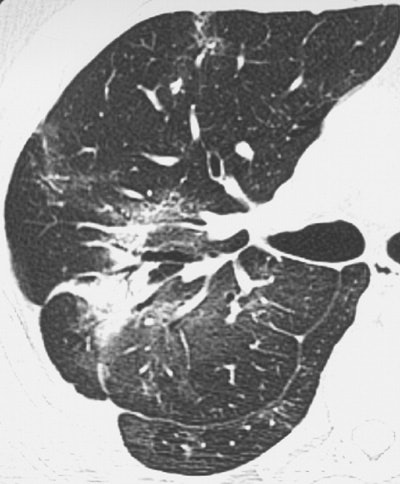

| Above (Fig. 2a), transverse conventional CT scan in 33-year-old man with SARS (obtained at day 4 after admission) shows ground-glass opacification. Below (Fig. 2b) follow-up thin-section CT scan (obtained at day 46 after admission, 29 days since discharge) of the corresponding area shows evidence of fibrosis, such as parenchymal bands, irregular interface, and traction bronchiectasis. Images and captions from Radiology Online, June 12, 2003, republished by permission of the author and the Radiological Society of North America, © RSNA 2003. |